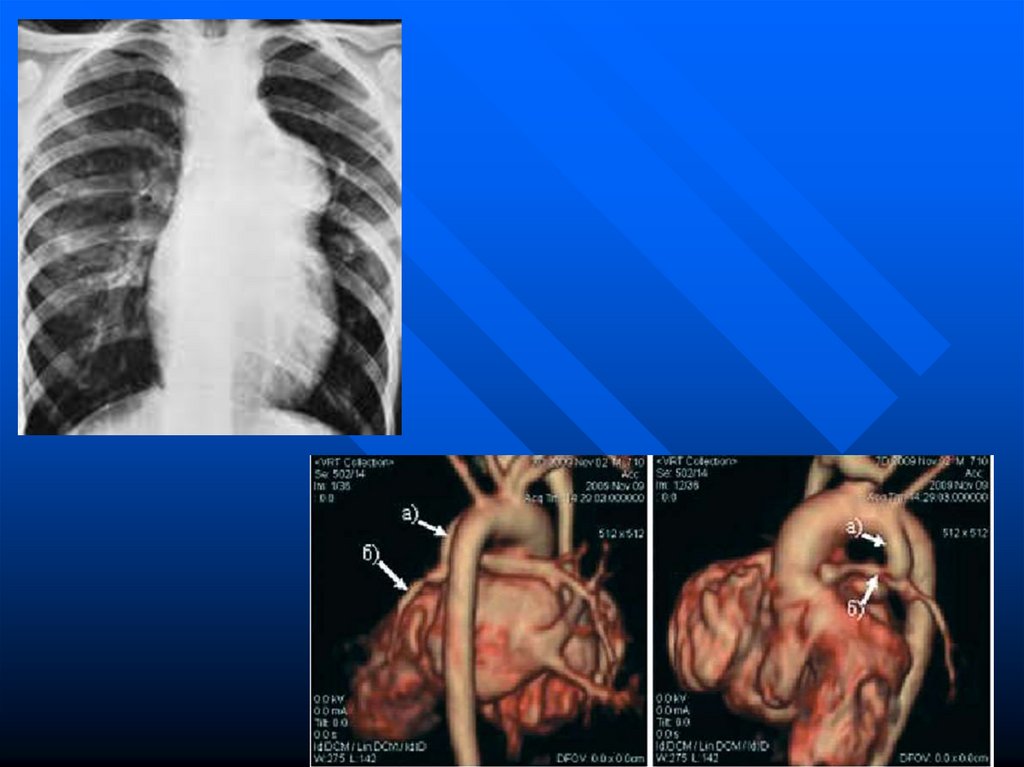

Структурное оформление сердца (оно

становится 4-камерным) и крупных

сосудов заканчивается на 7-8 неделях